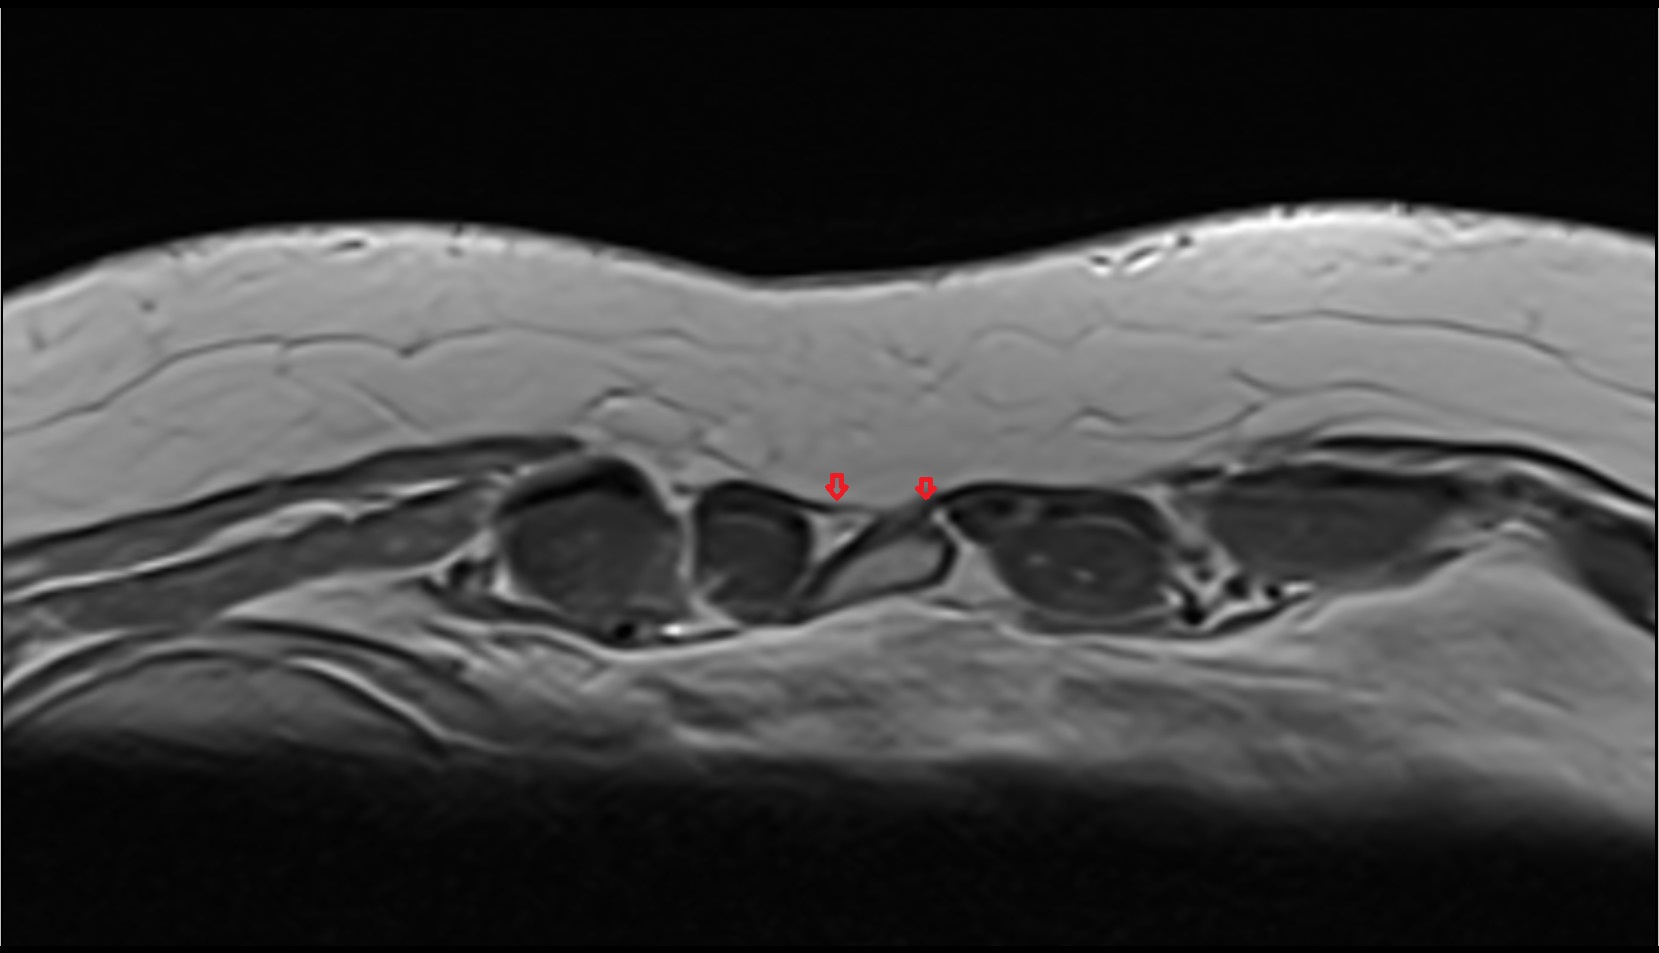

- Medial meniscus

- Lateral meniscus

- Anterior horn of medial meniscus

- Posterior horn of medial meniscus

- Anterior horn of lateral meniscus

- Posterior horn of lateral meniscus